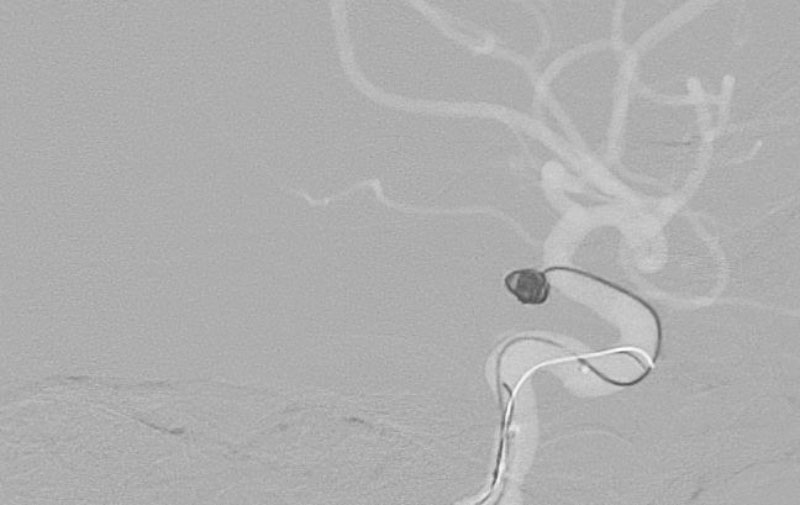

No.1593 手術前

No.1593 手術中

No.1593 手術後

'25年11月

くも膜下出血

右内頚動脈後交通動脈

分岐部動脈瘤破裂

60代

救急外来